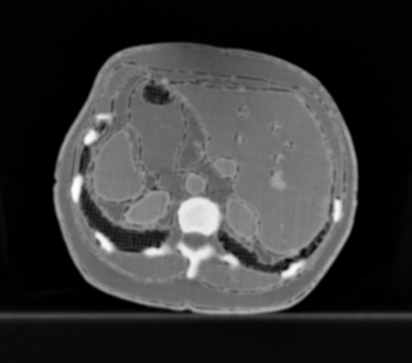

3.1.4 Example 3: Scanner settings impact in IQ

Changing CT scanner settings, like tube voltage or reconstruction geometry, has a direct impact in the noise distribution of the data, and thus in the quality of the reconstructed images. Here, we show an example of quality differences with acquired CT data from a realistic silicone phantom fabricated with multi-material extrusion 3D printing technology (citep \@BBN(Hatamikia et al., 2023)). The phantom model was derived from an abdominal CT and was fabricated with realistic radio density values which could mimic imaging properties of soft tissues in CT.

For the reference image, the anatomical phantom was scanned with the standard clinical CT protocol from SOMATOM Definition AS scanner, Siemens Healthineers, Erlangen Germany (tube current time product 70mAs for samples and 150mAs for anatomical phantom, tube voltage 120kVp, slice thickness 0.60mm, pixel spacing 0.77mm, iterative reconstruction kernel J30s). Additional scans with varying kVp values (80/100/120) as well as varying slice thickness (0.6/2mm) were also performed to assess the effect of the parameters on the image quality. We observed that changing kVp and slice thickness resulted in different image quality, where higher kVp and smaller slice thickness give the best visual result.

Refer to caption

(a) Reference

(b) (26.3, 0.88, 0.07)

(c) (28.2, 0.95, 0.03)

Figure 4: Comparison of image acquisition settings, (a) reference image with best chosen parameter setting (0.6mm and 120kVp), (b) preserves more detail (0.6mm and 80kVp) than (c) which is more smoothed (2mm and 100kVp). PSNR/SSIM misjudge the visual quality, LPIPS yields reasonable quality scores here.

FR-IQA mismatches

Although all IQA measures yield a better value for the image shown in Figure 4(c), a higher visual correspondence with the reference image can be seen in Figure 4(b) despite the black shadow in the bottom left corner. The image in Figure 4(c) with lower kVp yields a result that is too smooth in comparison to the reference. This yields another CT example where the IQA measures have been mislead by quality properties that are not relevant for the clinical application.